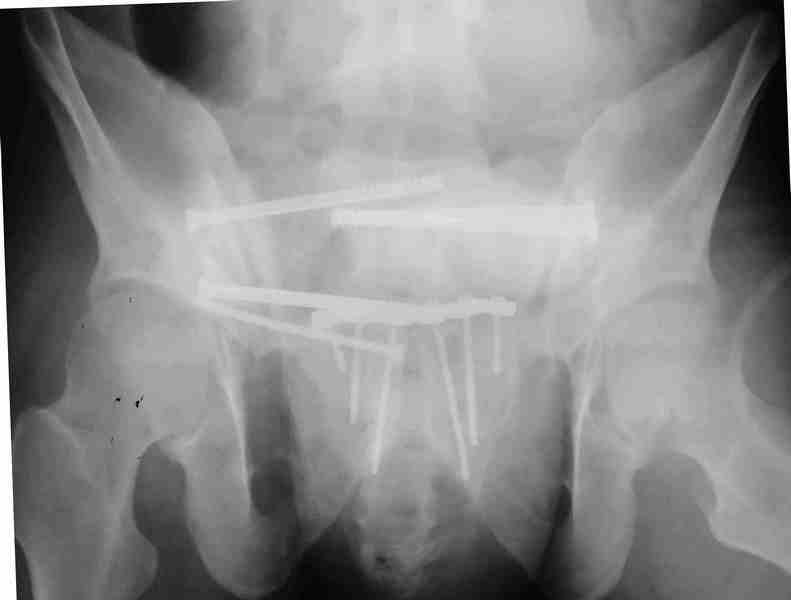

Молодой парень, без соматики. Сейчас чуть больше 2-х нед после операции, швы сняты, мочится сам. Был тяжелый, после операции дней 10 пытался выполнить лежа поперечный шпагат (успешно, так и лежал большей частью, может быть из-за обширной гематомы промежности). Репозиция не идеальная, но фиксация довольно надежная, за 2 нед ничего не "разъехалось". Сейчас пришел в ум. Когда по-вашему можно дать нагрузку и на какую ногу или на обе? Или вообще подскажете программу реабилитации.PS Заранее извиняюсь за качество снимков, до не делали (body scan), если не видно - то - полные разрывы КПС с двух сторон. после КТ сломался. Неврологии вроде бы нет.